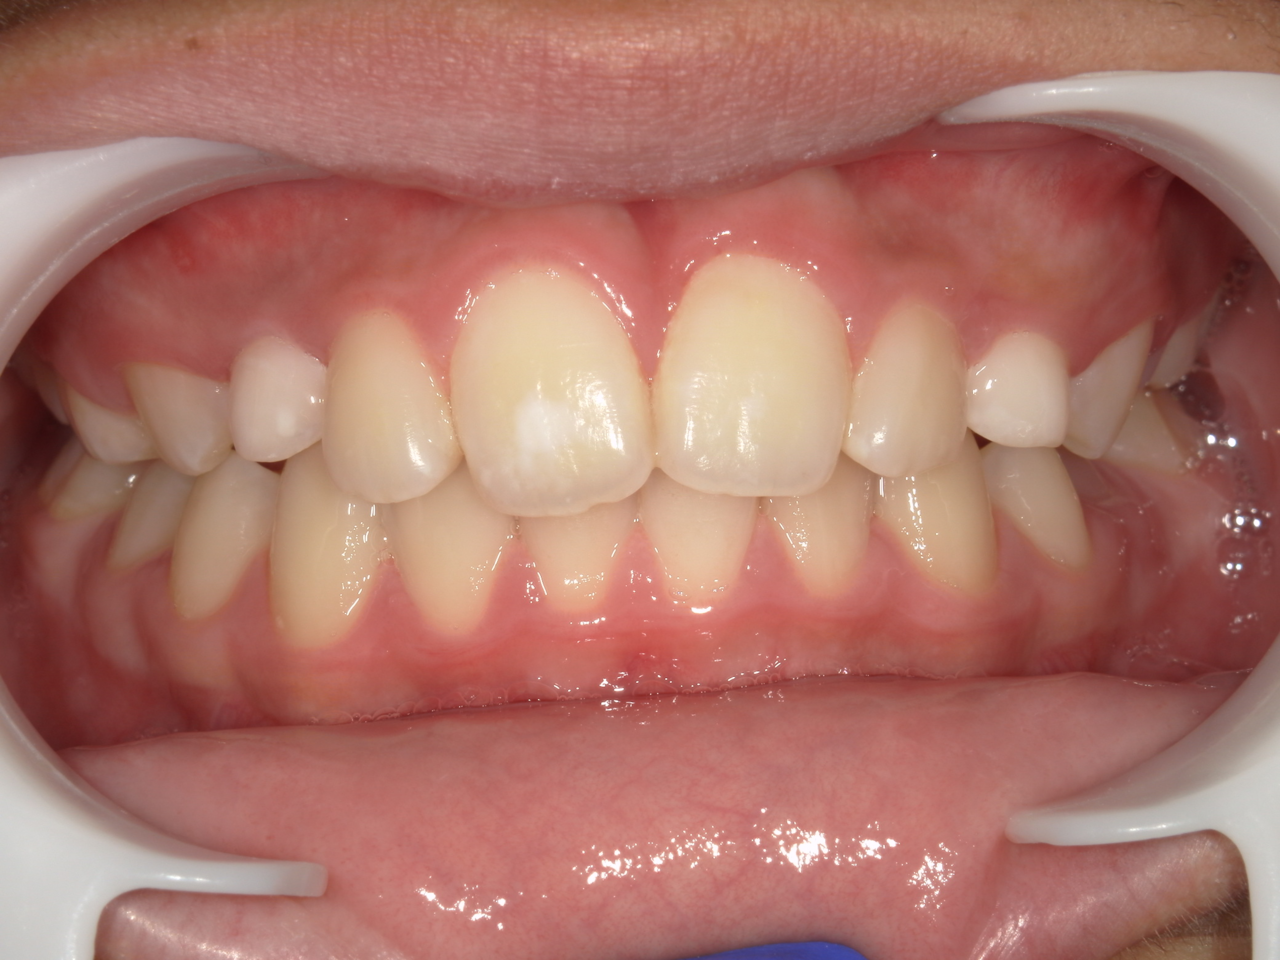

治療後

治療説明 歯科矯正で取り外し可能な矯正方法である床矯正で治療しました

治療期間 4年

治療費用200000 円

治療の副作用(リスク)歯の動き方には個人差があり、予想された治療期間が延長する可能性があります。。床矯正の使用状況、矯正歯科治療には患者さんの協力が必要であり、それらが治療結果や治療期間に影響します2次矯正が必要になる場合もあります。